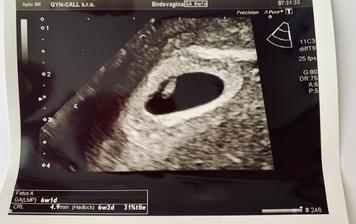

19.6. První kontrola u paní doktorky (6+1tt) - Všechno je v pořádku, miminko je tam, kde má být, velikostně odpovídá 6+2tt a srdíčko bije! Mám strašnou radost ♥ CRL 4,9mm. Na příště jsem objednaná na odběr krve ke screeningu a pokud bude v pořádku ultrazvuk, tak dostanu i průkazku!